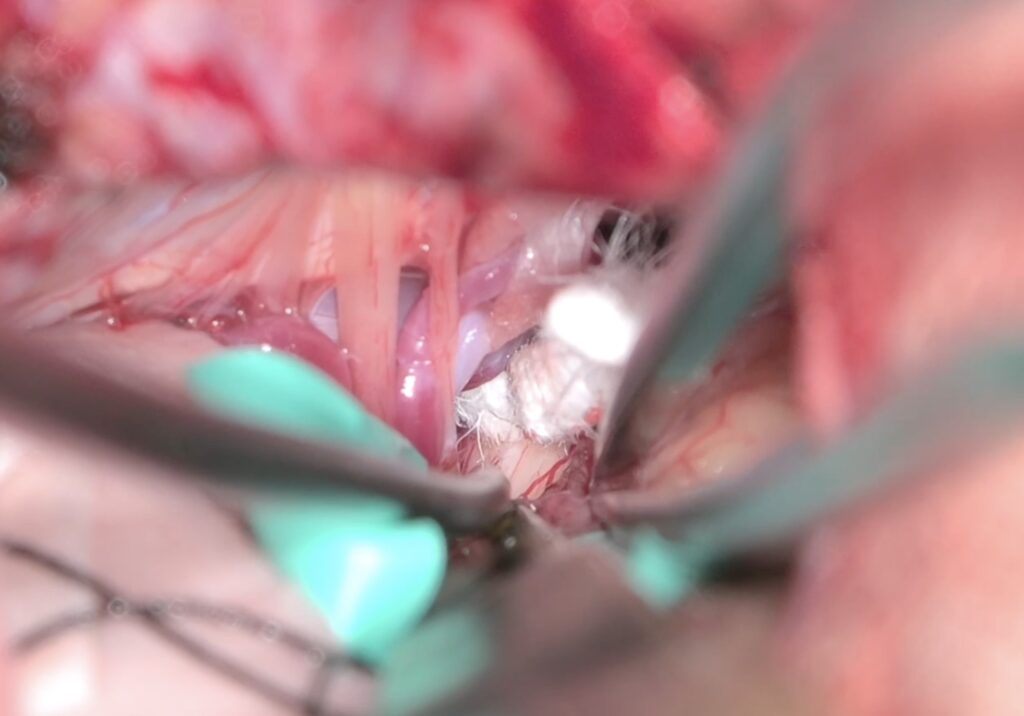

2603月 58歳女性の左顔面痙攣を治療しました。VAとAICAの複合型圧迫でしたがうまく治癒できました。